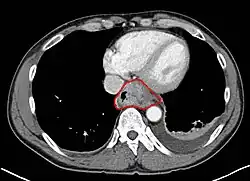

- AJCC divisions of the esophagus: (These are based on adjacent surgical landmarks)

- Cervical esophagus:

- Hypopharynx to the thoracic inlet, which is at the level of the sternal notch.

- By endoscopy, 15 to <20 cm from the incisors

- If thickening of the esophageal wall begins above the sternal notch, the location is cervical

- Upper thoracic esophagus:

- Thoracic inlet to lower border of the azygos vein

- By endoscopy, 20 to <25 cm

- Middle thoracic esophagus:

- Lower border of the azygos vein to the inferior pulmonary veins

- By endoscopy, 25 to <30 cm

- Lower thoracic esophagus and EG junction:

- Inferior pulmonary veins to the stomach; includes the intraabdominal portion of the esophagus

- By endoscopy, 30 to 40 cm